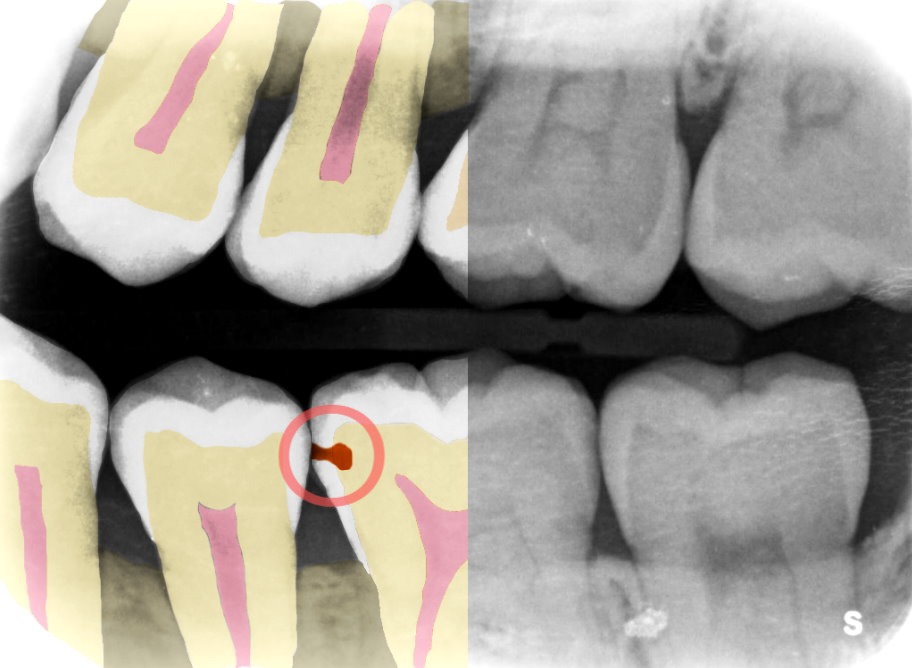

Ejemplo de software de Adra. Créditos de imagen: Adra

“Venimos del ojo de un dentista experimentado para ayudar a ilustrar los problemas convirtiendo los rayos X en imágenes para comprender mejor qué buscar”, agregó. “En última instancia, el dentista tiene la última palabra, pero nosotros aportamos el elemento de experiencia para ayudarlos a comparar y darles sugerencias”.

Al señalar rápidamente el problema y la extensión del mismo, los dentistas pueden decidir de qué manera quieren tratarlo, por ejemplo, hacer un empaste, un tratamiento con flúor o esperar.